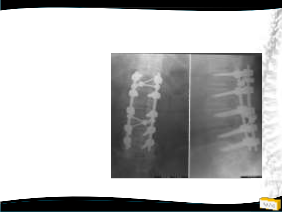

OLGU

• 54y, K

• Bel ve her iki bacak ağrısı

• NM normal

Yapılan Tedaviler

• 10 kilo verdi, egzersiz yaptı, FTR gördü

• 2009: Epidural steroid enjeksiyonu

– 6 Ay ağrısız

• 2010: Epidural steroid enjeksiyonu

– 3 ay ağrısız

– 1 ay ağrısız

2011

Tedavi ?

2009 2011